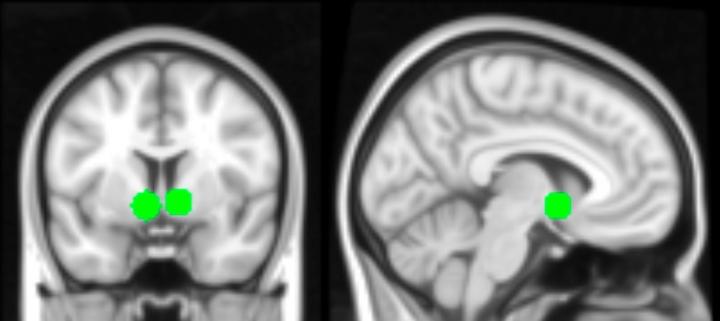

A region that was especially active is a part of the striatum called the nucleus accumbens, which is part of the brain's reward circuitry, she said. This reward circuitry is thought to be particularly sensitive during adolescence. When the teenagers saw their photos with a large number of likes, the researchers also observed activation in regions that are known as the social brain and regions linked to visual attention.